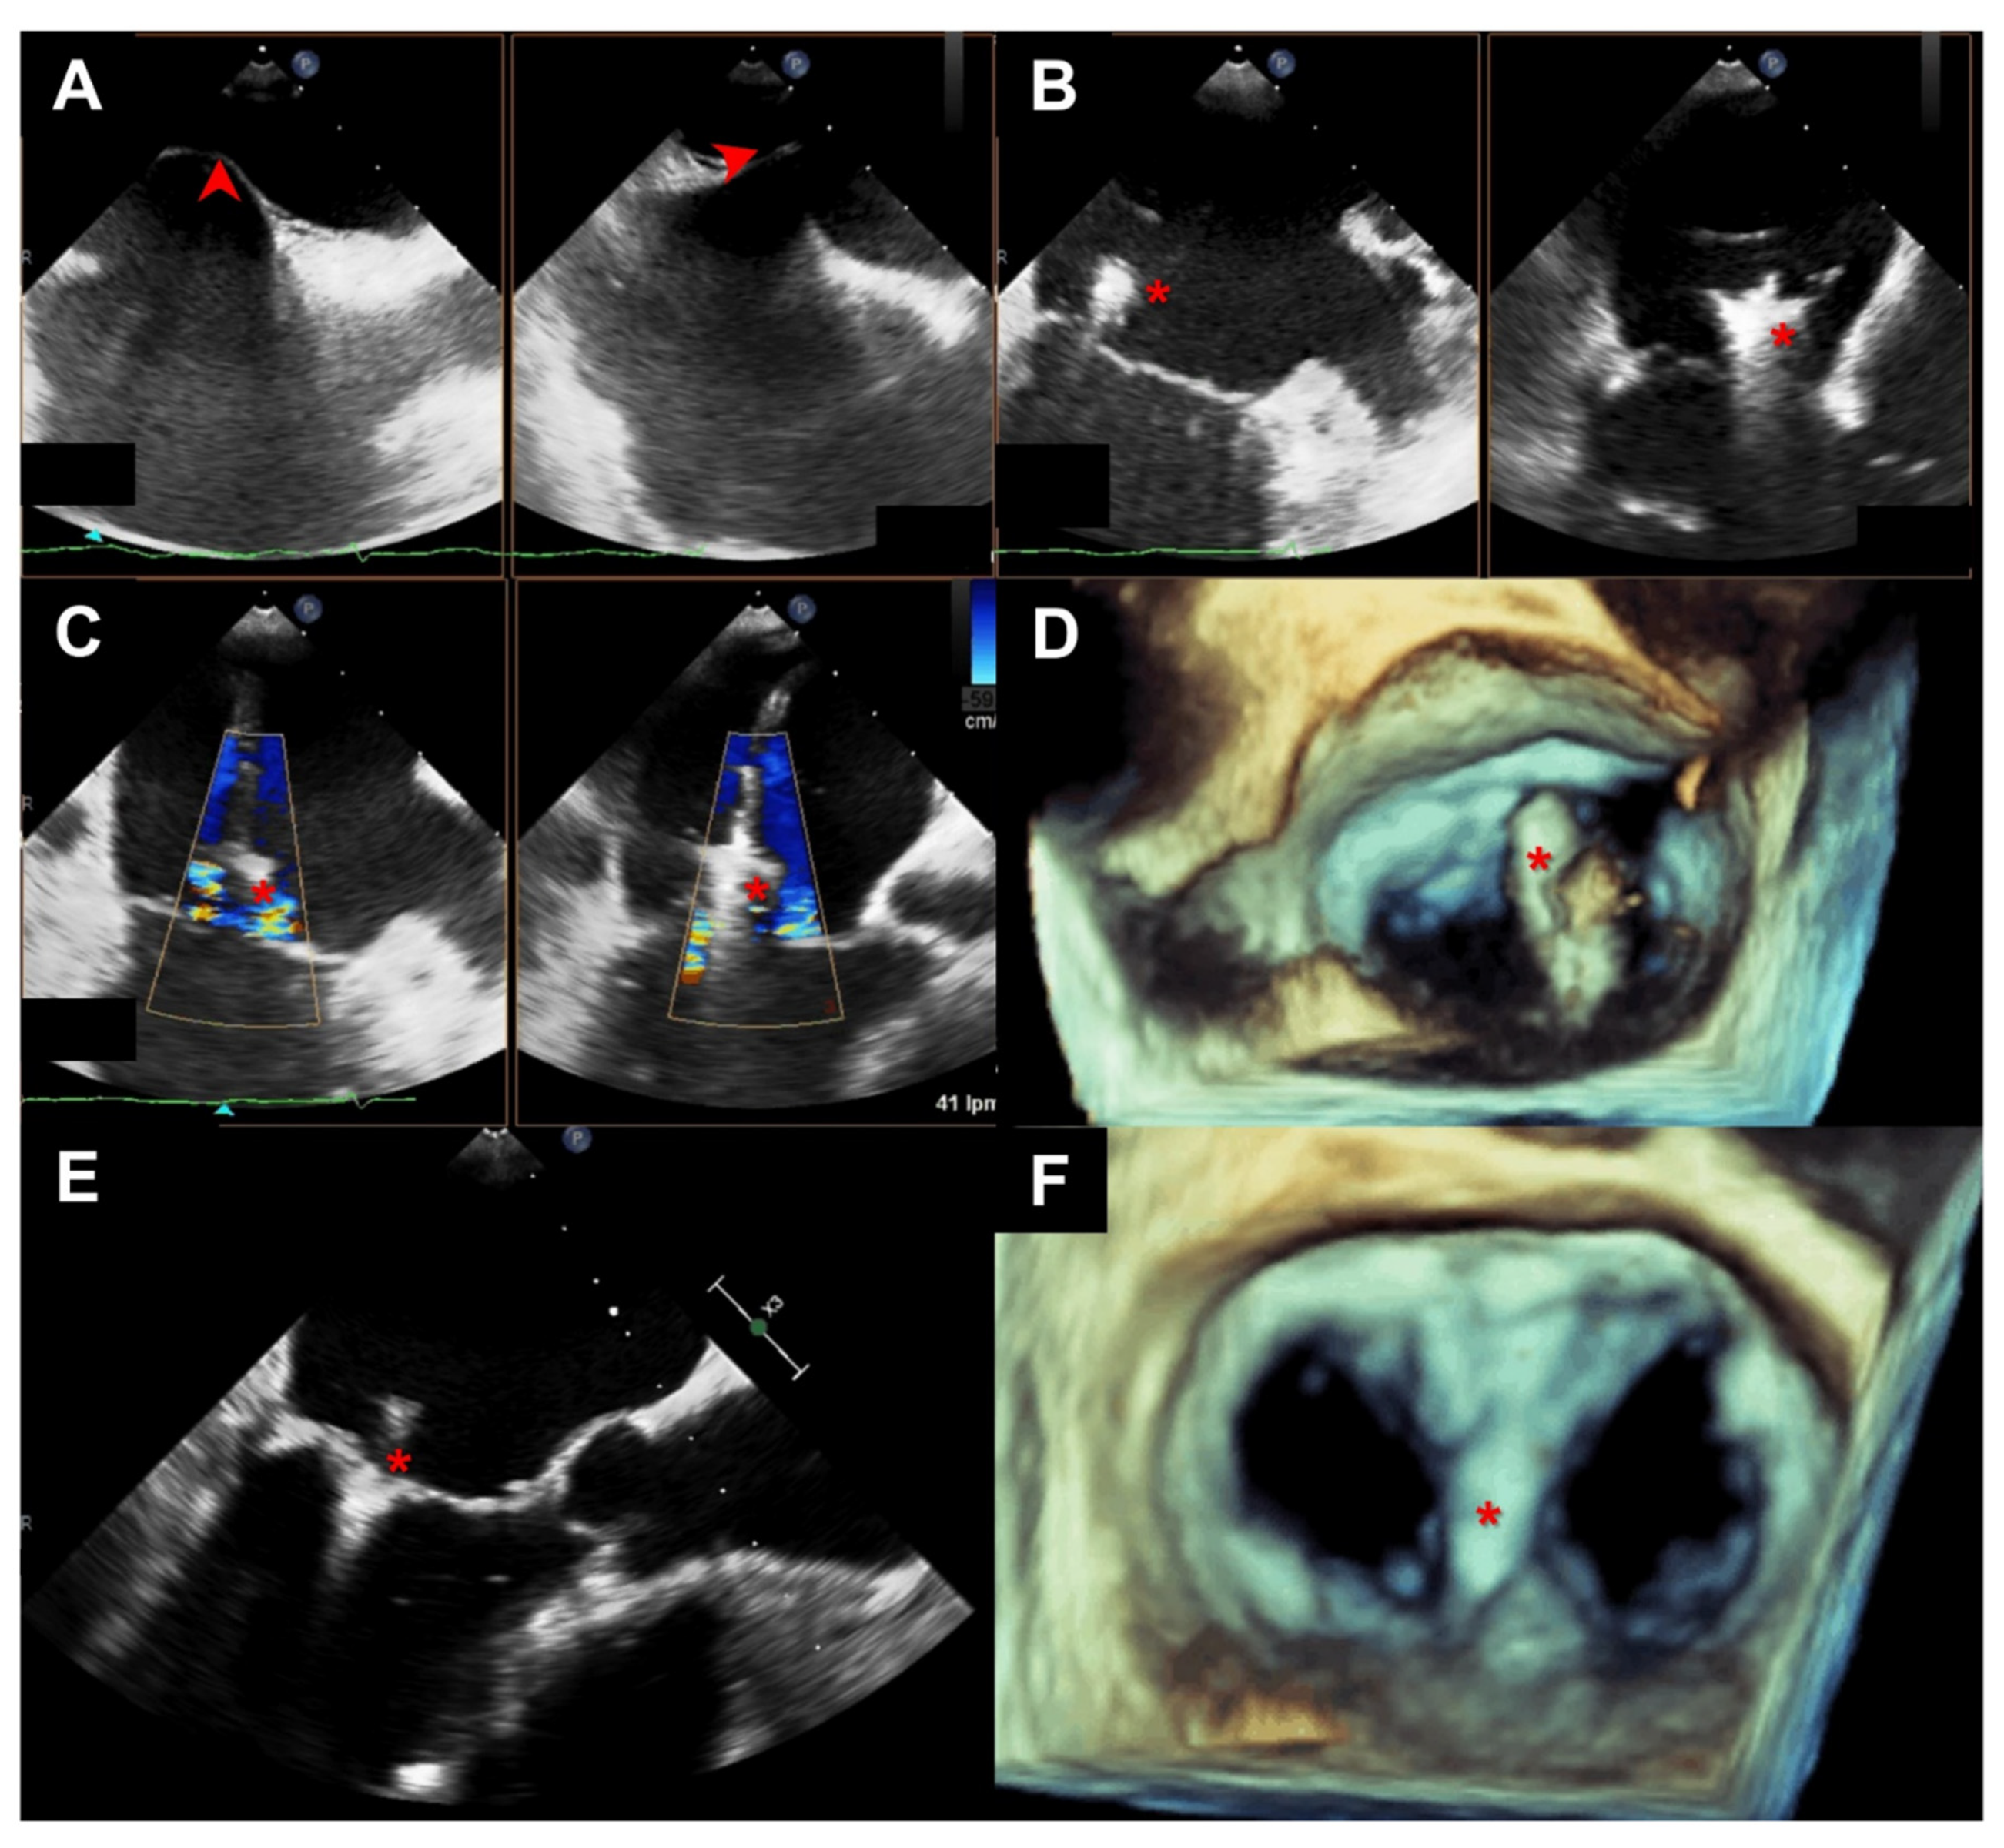

2.2. Echocardiographic Evaluation